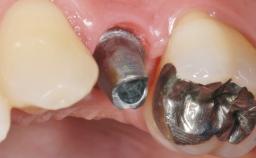

Early Placement of an Implant in a Maxillary Right Central Incisor Site

This 41-year-old female patient was referred to the clinic for the replacement of the right central incisor, since the tooth had developed a root fracture in the long axis that made extraction necessary. The healthy, non-smoking patient was first seen with the tooth still in place. A detailed Esthetic Risk Assessment was performed.The patient was worried about her dental esthetics and had high expectations for a successful treatment outcome from an esthetic point of view. The patient had a medium lip line that displayed parts of the gingiva in the anterior maxilla upon smile.

Defining Characteristics One missing tooth to be replaced by an implant-borne prosthesis

Bone Volume Deficient horizontally, allowing simultaneous augumentation